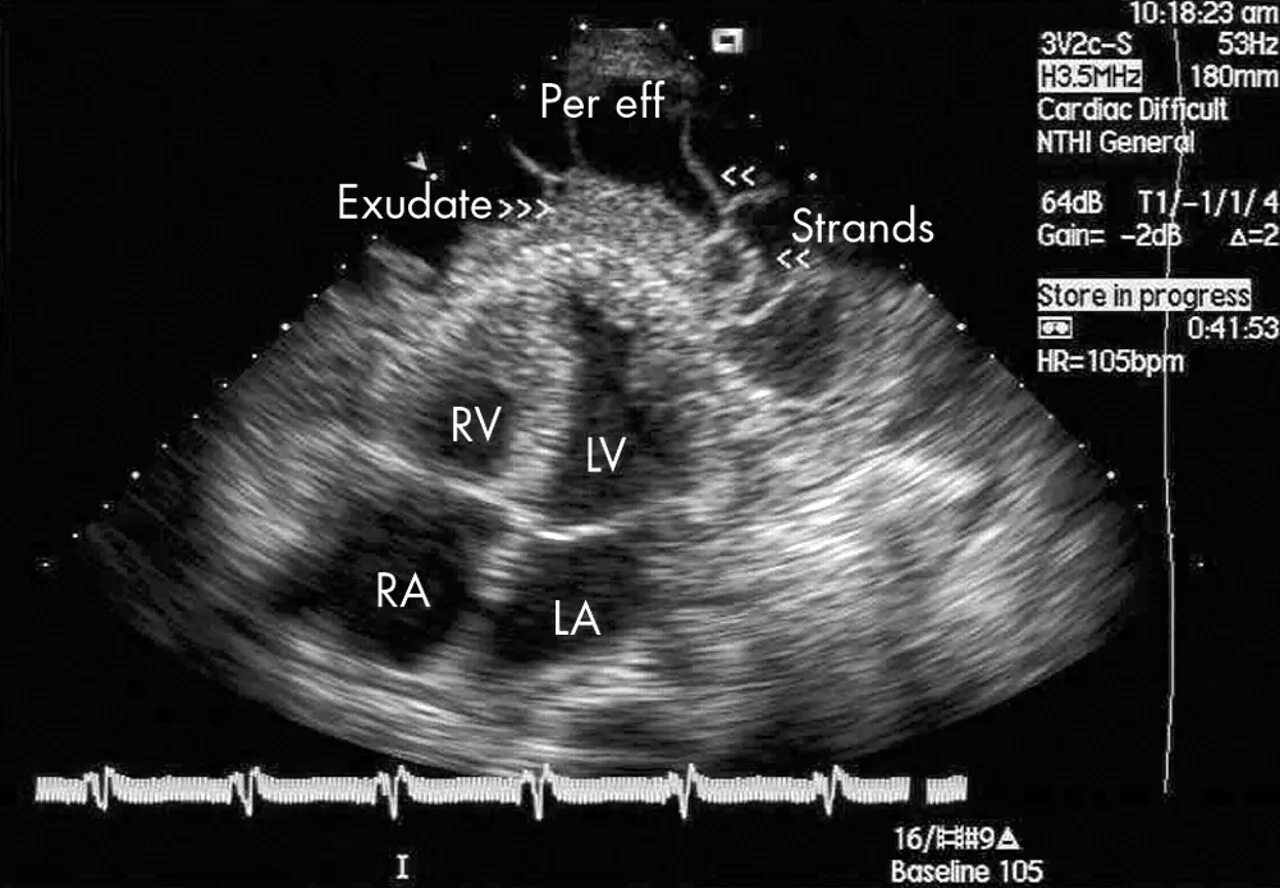

Экссудативный перикардит эхокг. острый фибринозный перикардит эхокг. эхокардиография сердца перикардит. экссудативный перикардит эхокардиография.

Перикардит эхокардиография. фибринозный перикардит на узи. эхокг эпикардиальный жир. констриктивный перикардит на эхо.

Экссудативный перикардит эхокг. экссудативный перикардит эхокардиография. экссудативный перикардит узи. фибринозный перикардит эхокг.